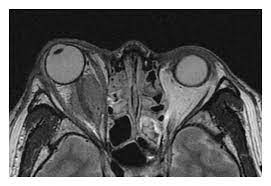

- 자기 공명 영상 (MRI): MRI 스캔은 목 부위의 디스크와 주변 조직을 자세하게 보여줍니다. 디스크의 헤르니에이션, 디스크 디게너레이션, 신경 굴곡 등을 평가하는 데 주로 사용됩니다.